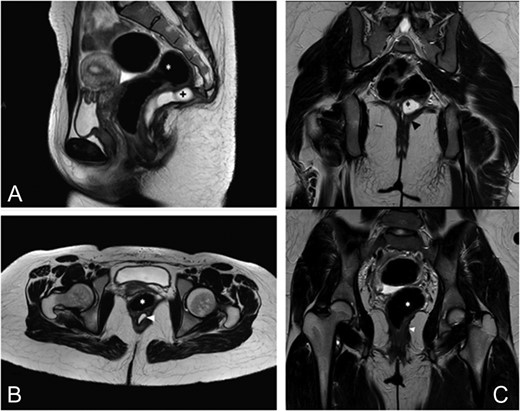

MRI (Magnetic Resonance Imagery) and endorectal-US revealed a wide, homogeneous, multiloculated cystic lesion (8.8 × 8.3 × 10 cm3). The mass lay on the right posterolateral pararectal space, in an extraperitoneal plan, following the course of the rectal distal portion in the context of the levator ani muscle. At IV contrast injection scans no significant contrast agent uptake by the lesion was detected (Fig. 1A–C).

Preoperative MRI. (A) Axial TSE T2-weighted images show a large multiloculated cystic lesion (arrowhead) dislocating and closely adherent to the posterior rectal wall (*). (B) This sagittal TSE T2-weighted image shows a cystic lesion (arrowhead) expanded in the posterior pararectal space, containing serum-proteinaceous material, following the course of the rectal distal portion (*) in the context of the levator ani muscle. (C) Coronal TSE T2-weighted images demostrate the relations among the cystic lesion (black*), the rectum (white*) and the levator ani muscle (arrowhead).